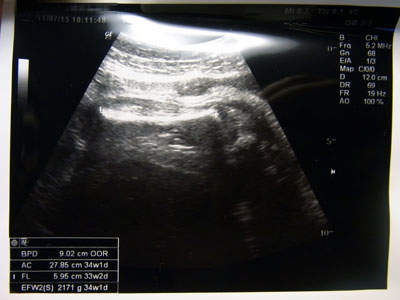

おママの定期検診。

確かに胎児は大きいが、正常の範囲だって。

何が何だかわからない。

正常の範囲というので少し安心したが、

おママのお腹は最高潮に巨大化している。

そして胃が圧迫されるのか、食後少し気分が悪くなったそうだ。